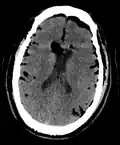

CT scans of patients with a tension pneumocephalus typically show air that compresses the frontal lobes of the brain, which results in a tented appearance of the brain in the skull known as the Mount Fuji sign.[1][2][3] The name is derived from the resemblance of the brain to Mount Fuji in Japan, a volcano known for its symmetrical cone. In typical cases, there is a symmetrical depression near the midline (such as the crater of a volcano), due to intact bridging veins.[3] Its occurrence seems to be limited to tension pneumocephalus (not occurring in pneumocephalus without tension).[4] The sign was first described by a team of Japanese neurosurgeons.[5]